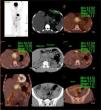

Case ReportA 36-year-old male patient presented to the hospital with complaints of abdominal pain and constipation. He was evaluated through detailed anamnesis and physical examination. The patient was found to have iron deficiency anemia and elevated acute phase reactants. An abdominal ultrasound revealed a mass in the epigastric region, leading to admission to the gastroenterology department. A CT scan of the abdomen showed a 62 × 55 mm lesion in the epigastric region. A tru-cut biopsy was performed, which was reported as amyloidosis. The biopsy revealed an increase in plasma cells. A PET-CT scan identified hypermetabolic lymph nodes in the celiac trunk region.

A biopsy taken from these nodes was also reported as amyloidosis, with no evidence of monoclonality. Results showed positivity for CD138, Kappa, Lambda, Congo red, and IgG4, with negativity for HHV8.

Serum IgG level was 3256 mg/dL, albumin was 3.59 g/dL, total protein was 8.59 g/dL, sedimentation rate was 65 mm/h, and elevated levels of free kappa and lambda light chains were detected. The patient developed renal failure and hyperkalemia. A renal biopsy showed positive staining for AA amyloid, and a bone marrow biopsy was subsequently performed. The PET-CT scan did not reveal plasmacytoma or osteolytic lesions. The bone marrow biopsy showed 7-8% staining with CD38 and CD138.